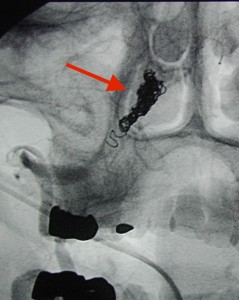

<右解離性椎骨動脈瘤:矢印>

<コイル:矢印>